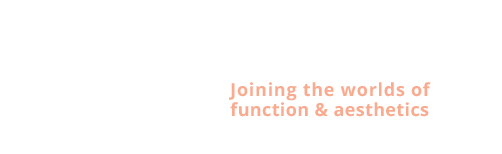

James: jaw surgery and implants - one surgery.

Diagnose van het gezicht

- Te kleine onderkaak (Overbeet)

- Asymmetrisch gezicht